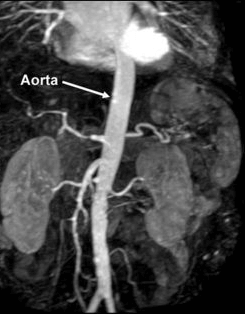

BT anjiografide de hasta tekerlek şeklinde bir cihazın içine yatırılarak önce kol toplardamarından damarları boyayan bir ilaç verilir. Daha sonra hızlı bir şekilde vücudun incelenecek kısmından kesit şeklinde çok sayıda tomografi görüntüleri alınır. Bu ince kesitler bilgisayar ortamında birleştirildikten sonra da üç boyutlu anjiografi görüntüleri elde edilir.

BT anjiografide de tıpkı MR anjiografide olduğu gibi vücuttaki tüm damarlar incelenebilir. Özellikle koroner kalp damarlarının incelenmesinde günümüzde klasik kalp anjiosuna alternatif bir yöntem haline gelmiştir. Ayrıca karın, beyin ve boyun damarlarının görüntülenmesinde de birçok durumda klasik periferik anjiografinin yerini almıştır. Görüntüler MR’ a göre daha net olduğundan ve hareket artefaktlarından daha az etkilendiğinden, BT anjiografi görüntüleri MR anjiografiye göre daha kaliteli ve güvenilirdir. Ancak BT anjiografide hasta radyasyon alır ve mutlaka damardan ilaç (kontrast madde) vermek gerekir. Bu ilaç özellikle böbrek yetmezliği olan hastalarda dikkatli kullanılmalıdır. Ayrıca her incelemede sınırlı bir alan taranabilir. Bu özellikleriyle BT anjiografi genellikle klasik anjiografi yapmadan önce uygulanan ve bazı hastalarda klasik anjiografinin yerini tutabilen bir yöntemdir. En önemli üstünlüğü sadece damarın içini değil damar duvarını da gösterebilmesi ve duvar içinde yer alan kan, pıhtı ya da henüz damarda belirgin tıkanma yaratmayan ateroskleroz gibi patolojileri de gösterebilmesidir.